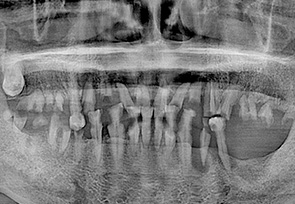

• before

• after